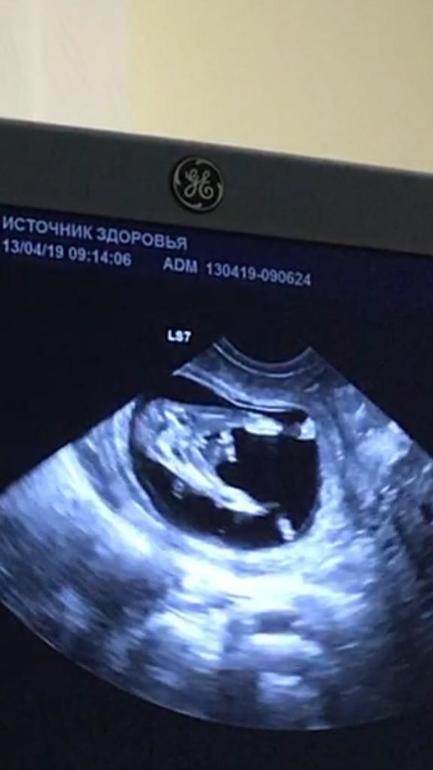

Сходила сегодня на скрининг в ЦПСиР, какие там все душевные и добрые! Очень мне все понравилось, на УЗИ без очереди, на кровь 2-3 чел подождала, но все быстро и с улыбкой.

С ребеночком все хорошо, все в норме, КТР уже 6,1 см, а ТВП стал 1,4, а было 2 дн...